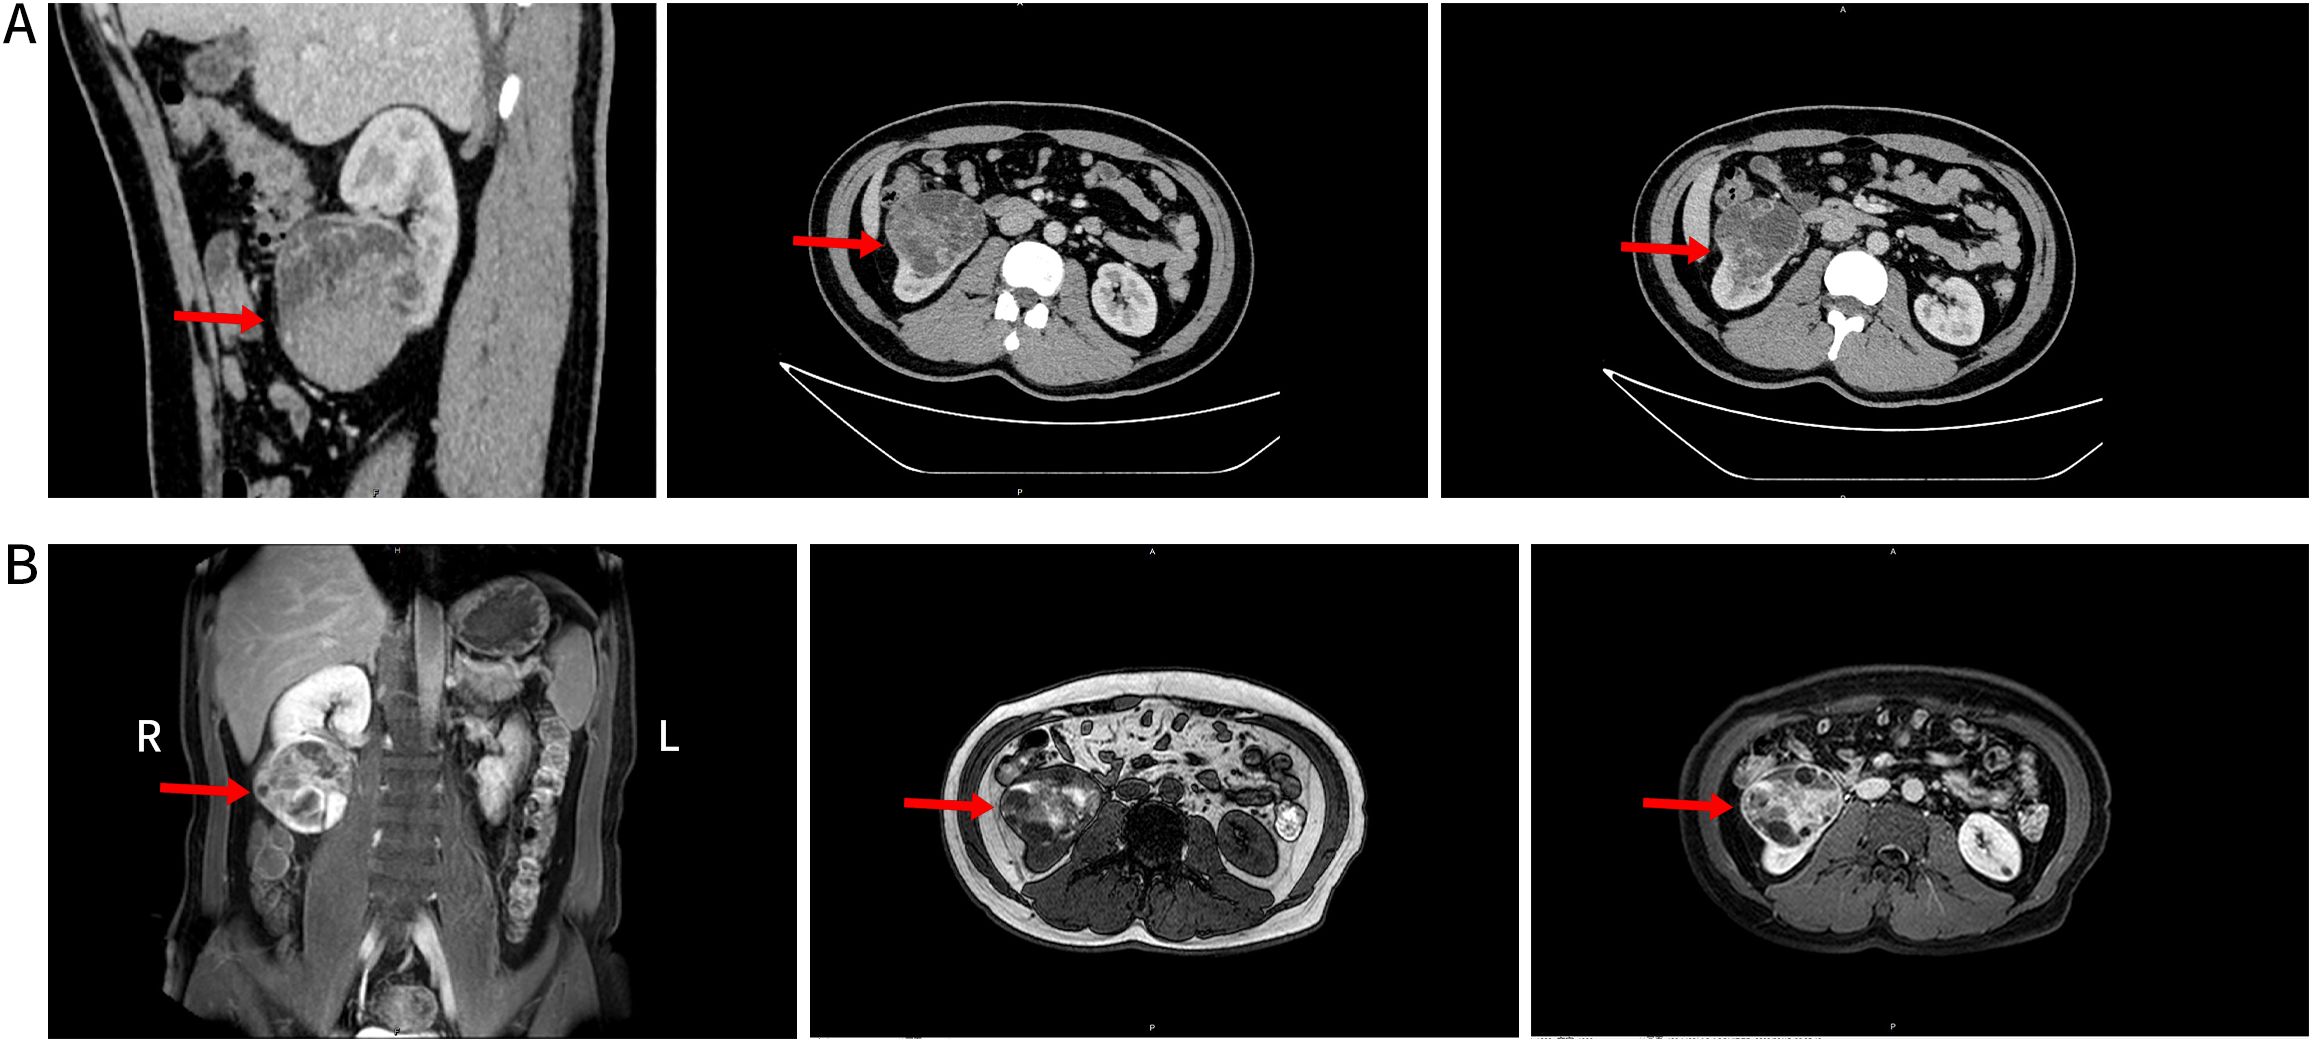

Background: Angiomyolipoma with Epithelial Cysts (AMLEC) is a rare renal tumor that has been established as a separate pathological entity in recent years. Existing literature has focused on its histological origin, molecular features, and imaging characteristics. To our knowledge, this is the first reported case of AMLEC coexisting with clear cell renal cell carcinoma (ccRCC). Case presentation: A 37-year-old male presented with lumbar pain and persistent gross hematuria. Imaging revealed tumor rupture with hemorrhage, initially suggestive of cystic renal cell carcinoma. However, postoperative pathology and immunohistochemistry confirmed a diagnosis of AMLEC combined with ccRCC. Conclusion: AMLEC is a rare subtype of angiomyolipoma (AML) that typically lacks adipose tissue, with an epithelial component likely derived from dilated renal tubules. Its unique histological features and immunohistochemical staining are key to pathological diagnosis. This report also reviews prior cases of AMLEC and synchronous renal tumors, offering a valuable reference for clinical diagnosis and management.